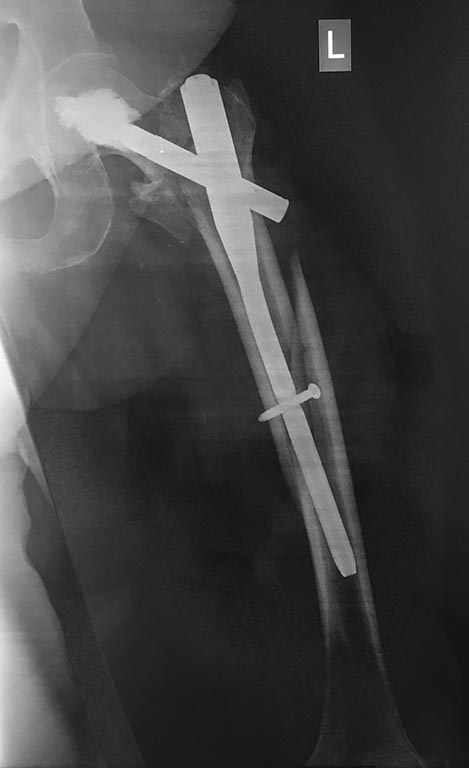

Здесь первое наше наблюдение такого остеосинтеза с нестабильной ножкой. Прошло уже 6 лет - вот недавние снимки. Пациент не имеет жалоб, катается на коньках. Никакие дистальные винты не выдержали бы циклических нагрузок столько лет, если бы ножка оставалась нестабильной.

Как только увидел снимок, сразу промелькнула мысль - на старый гвоздь одеть новый ретроградный, именно это первым делом порекомендовал Шнеттлер. Отличные кейсы на этот счёт продемонстрировали Александр Николаевич и Алексей Юрьевич. По-моему, это очень даже reasonable вариант, учитывая аугментацию головки и остеопороз проксимального отдела.